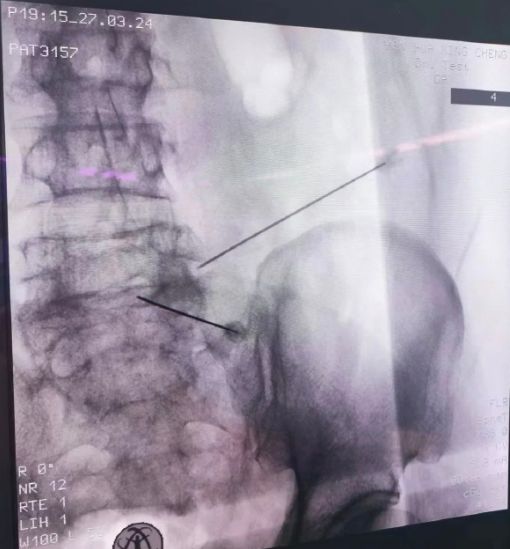

不管是中医外治还是西医微创,精准找到病灶都至关重要。我们借助超声、C型臂这些“医学火眼金睛”,能清清楚楚看到哪根神经在“闹别扭”。比如患者说“腰侧疼”,医生就能用超声当“眼睛”,精准定位受损神经后再施治,既不浪费药物,也不会伤到健康神经,为后续中西医治疗打下坚实基础。

来星城疼痛科后,我们先全面评估曹阿姨的情况:虽已进入神经痛期,但她体质偏虚、气血不足,单纯微创治疗虽能快速止疼,却难解决体质虚弱导致的恢复慢、易反复问题,因此确定了中西医结合的调理方案。我们先通过超声定位找到受损的颈椎脊神经,实施神经阻滞治疗精准快速止痛;同时根据她的体质开具个性化中药方剂调理气血,搭配温和的针灸治疗舒缓神经、促进恢复。